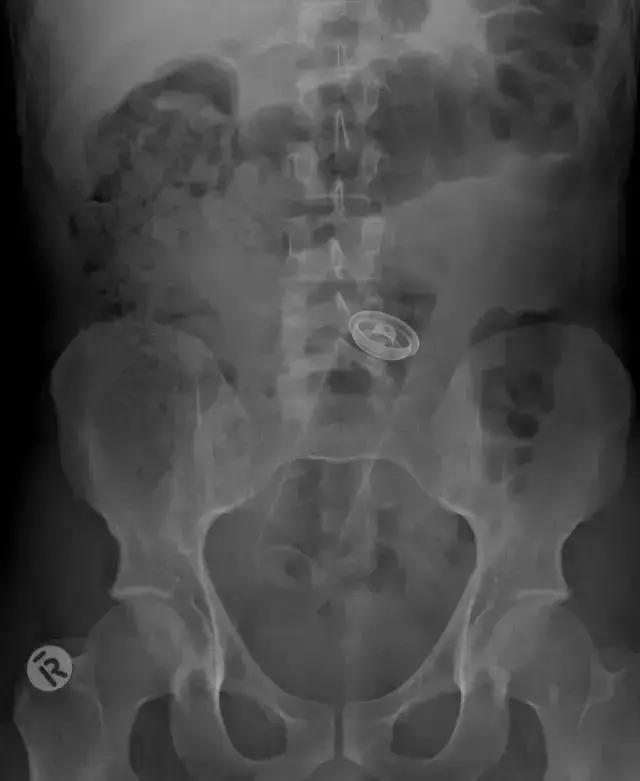

▲X光片中,胃里的刀片清晰可见

▲犯人私藏的手机